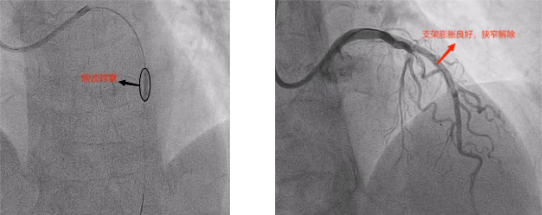

手術(shù)中,心血管內(nèi)科介入團(tuán)隊精準(zhǔn)操作:先將振波球囊送到血管鈣化部位,隨后啟動低頻沖擊波。與傳統(tǒng)球囊的“強力擴(kuò)張”不同,振波球囊釋放的沖擊波能夠穿透血管壁,在不損傷正常組織的情況下,將堅硬的鈣化斑塊“震碎”成細(xì)小顆粒,為血管“松綁”。術(shù)中影像顯示,鈣化斑塊逐漸松解,血管通道被成功拓寬。確認(rèn)鈣化處理效果后,團(tuán)隊迅速植入了支架。術(shù)后造影顯示,支架固定良好,血流恢復(fù)通暢,整個手術(shù)僅用時40分鐘。